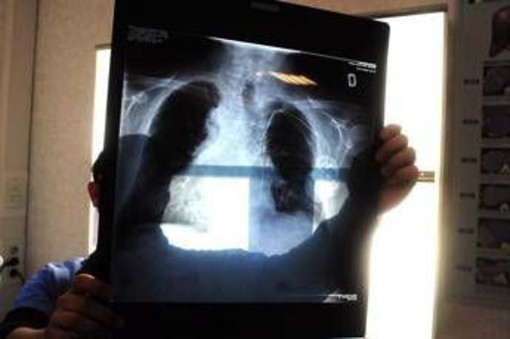

Ogni anno in Europa si registrano circa 63mila-72mila nuovi casi di tumore polmonare a piccole cellule (Sclc). La maggior parte di questi pazienti riceve una diagnosi di malattia in stadio esteso, aggressiva e spesso difficile da trattare, con prognosi infausta. IMforte - informa una nota - è il primo studio globale di fase 3 a dimostrare benefici clinicamente significativi in termini di Pfs e Os nel trattamento di mantenimento di prima linea per Es-Sclc e stabilisce la terapia di mantenimento con lurbinectedin più atezolizumab come nuovo standard di cura per i pazienti. I dati dello studio, pubblicati contemporaneamente su 'The Lancet', sono serviti come base per la presentazione della supplemental New Drug Application (sNda) all'agenzia americana Fda da parte di Jazz Pharmaceuticals, nonché per la presentazione di una domanda di autorizzazione all'immissione in commercio (Marketing Authorisation Application, Maa) all'Agenzia europea per i medicinali (Ema) da parte di PharmaMar.

"Il carcinoma polmonare a piccole cellule è una patologia complessa - spiega Filippo de Marinis, direttore della Divisione di Oncologia toracica dell'Istituto europeo di oncologia (Ieo) Irccs di Milano - Al momento della diagnosi, la grande maggioranza dei pazienti presenta già una malattia in stadio esteso e dispone di opzioni terapeutiche molto limitate. In Italia, si registrano ogni anno oltre 40mila nuovi casi di tumore del polmone, circa il 15% dei quali è rappresentato dal carcinoma a piccole cellule. I risultati dello studio IMforte sono molto promettenti e indicano una potenziale opzione terapeutica in grado di modificare la pratica clinica e migliorare significativamente l'esito per pazienti con un importante bisogno medico insoddisfatto".